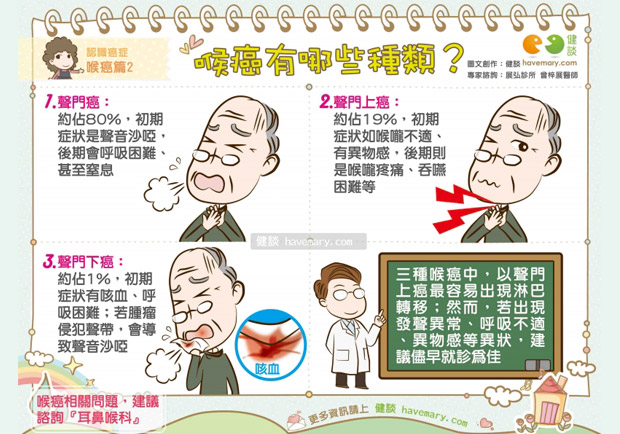

喉癌2 Vital Strategies Media Beacon

喉癌预防 咽喉癌的早期症状 喉癌是怎么引起的 喉癌的症状 喉癌基础

存活率不到3成 咽喉癌早期8大症狀要注意 連聲音 沙啞 也要警惕 每